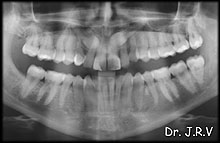

| Foto 5A.- Rx Panorámica en la que se observan los caninos superiores permanentes

incluidos. |